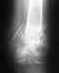

Добрый день!У меня был вывих средней фаланги 2 (указательного) пальца руки. Сразу обратился к травматологу, но он не увидел на снимке вывиха и сказал, что просто ушиб. Через 2 недели, после того, как подвижность сустава не восстанавливалась, обратился в поликлинику к хирургу, сделали снимок, на котором был виден вывих. В травматологическом отделении открытым способом вправили сустав и зафиксировали спицей на 4 недели. 2,5 недели назад спицу сняли, сказали разрабатывать сустав. Сустав сейчас до конца не разгибается, сгибается только на 90%. Сам сустав на ощупь неестественно большой по сравнению со здоровым. Постоянно пытаюсь согнуть палец в суставе. Подскажите пожалуйста что можно и нужно делать чтобы разработать сустав. Что вообще сейчас просходит с суставом. Не может ли сустав остаться с такой подвижностью навсегда. Как этого избежать. Заранее спасибо за ответ.

Прочитал сейчас свой пост, и увидел что непонятно написал. На самом деле если исходить из того, что полная подвижность это 100%, то сустав не разгибается на 25% и сгибается на 25%, и соответственно чтобы до конца согнуть его необходимо еще 50%. Врач посоветовал с силой сгибать палец и разгибать, я так и поступаю. Может быть я зря паникую, и со временем все восстановиться, но наученный горьким опытом общения с первым травматологом, хотелось бы услышать мнение других специалистов.